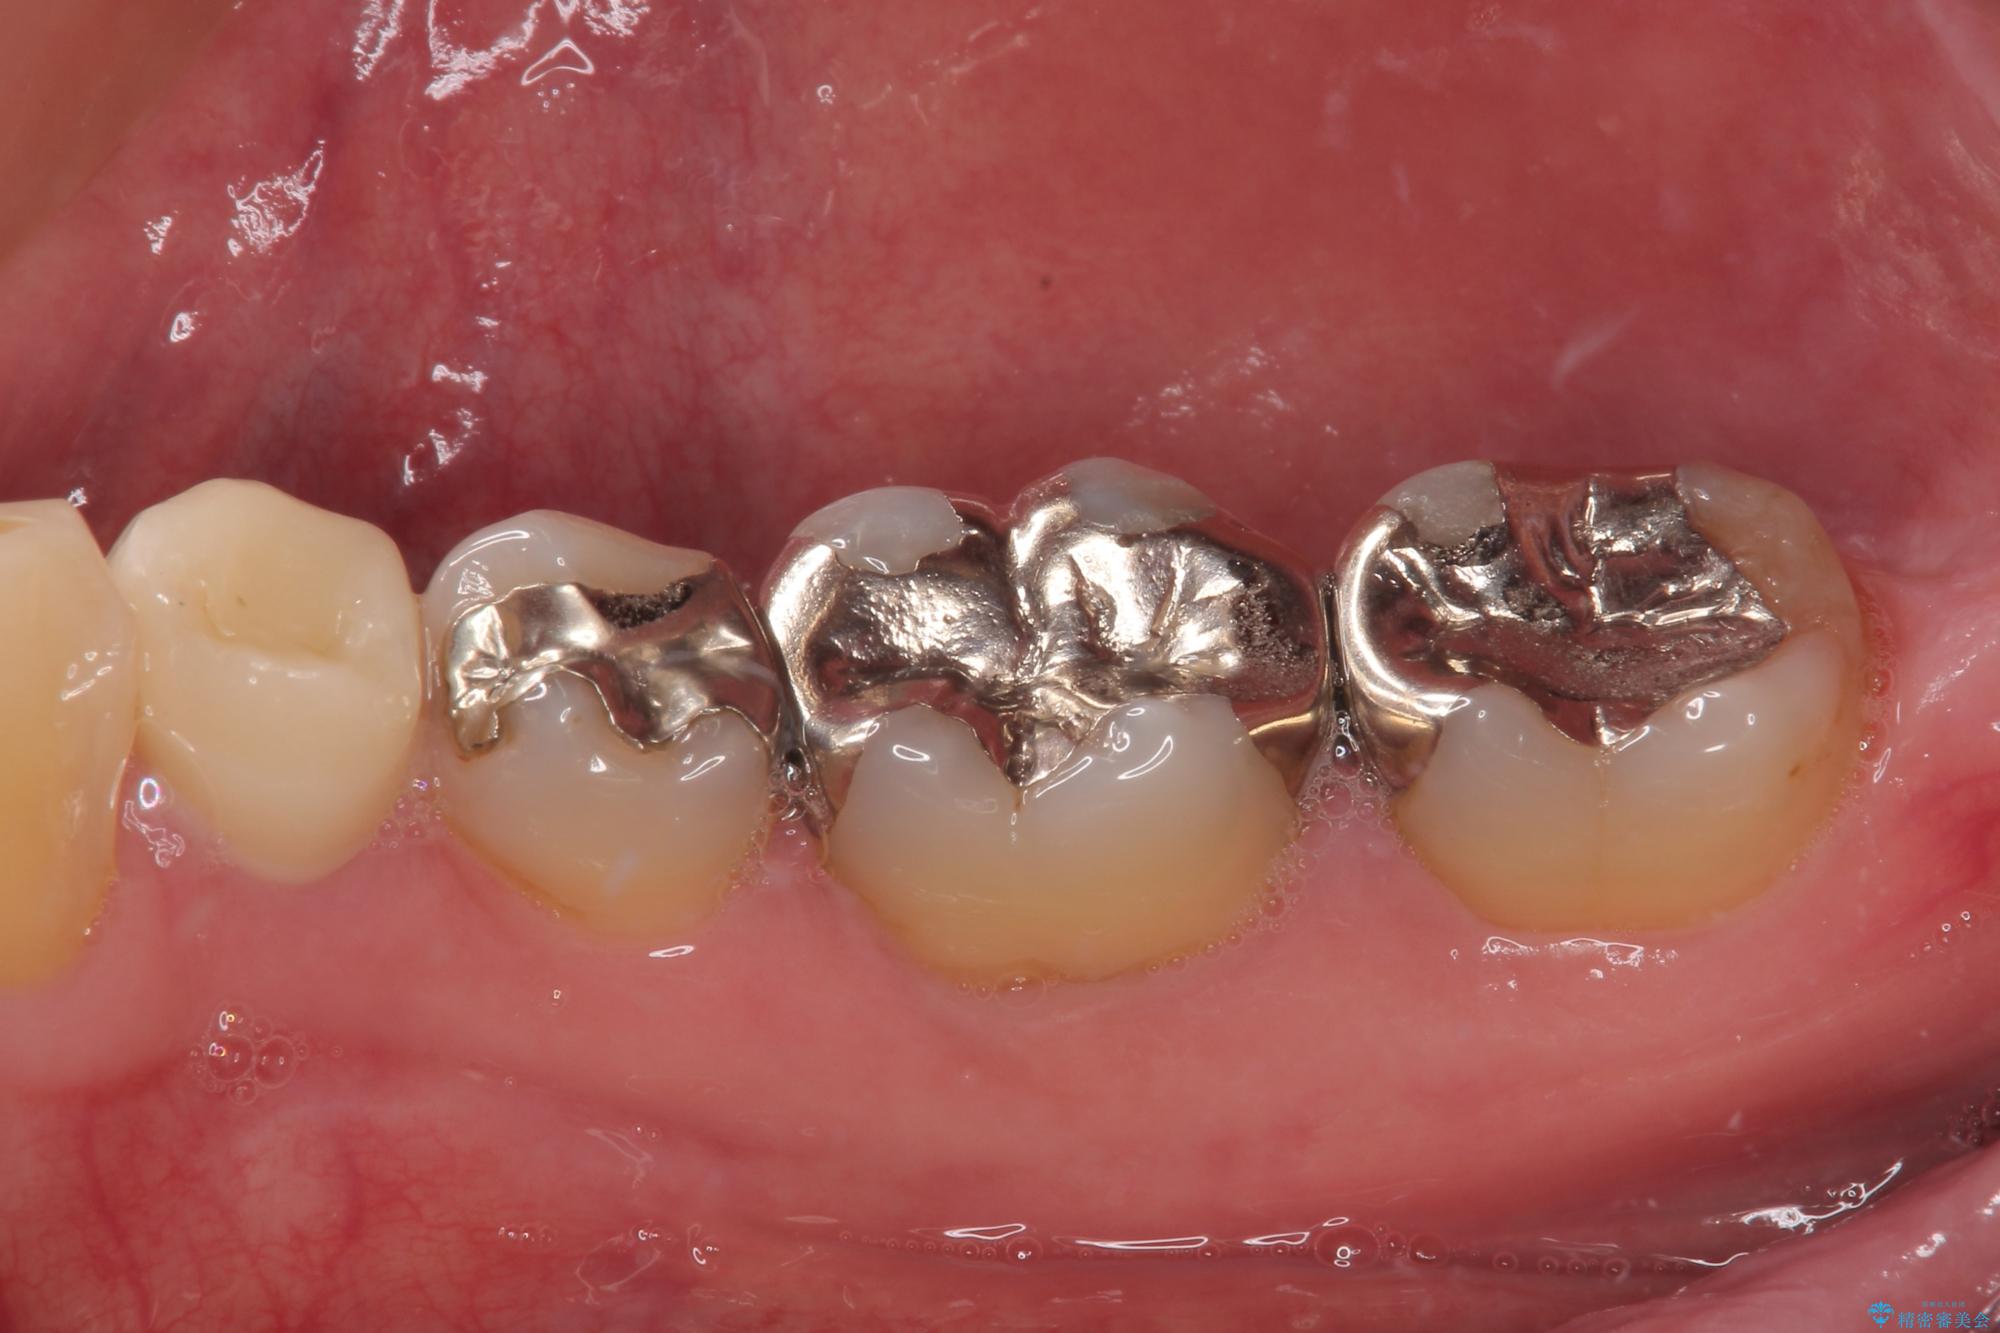

- 右下の銀歯が取れたとのことで来院された患者様です。以前にも取れていたところで、メタルインレーの不適合も認めていたため、次回外れたらオールセラミッククラウンにやり替えていくことを説明していたため、オールセラミッククラウンによる補綴治療を行っていくことにしました。

拡大鏡視野下で虫歯を除去しオールセラミッククラウンに適した形に整えました。